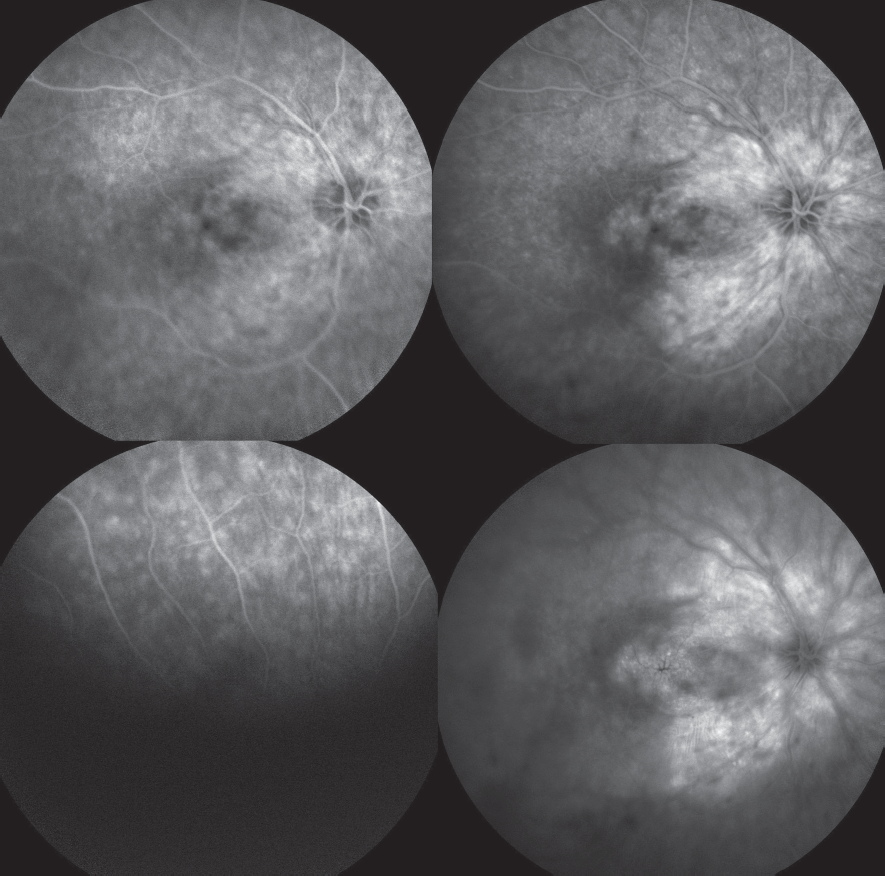

Пациент в возрасте 35 лет обратился на консультацию в Центр диагностики и хирургии заднего отдела глаза для получения «второго мнения» и определения тактики ведения. За два года до обращения в Центр диагностики и хирургии заднего отдела глаза на основании данных флюоресцентной ангиографии пациенту был поставлен диагноз идиопатического ретинального васкулита. В течение 1,5 года пациент получал циклоспорин А в дозе 350 мг и преднизолон (последний год в дозе 20 мг). На осмотре пациент предъявлял жалобы на низкую остроту зрения обоих глаз. Известно, что в возрасте 7 лет у пациента диагностирован миопический астигматизм средней степени обоих глаз. Дату снижения зрения пациент указать не может, считает своё зрение «плохим с детства». Максимально корригированная острота зрения (МКОЗ) правого глаза — 0,2, МКОЗ левого глаза — 0,2. Передний отрезок спокойный, клеток и флёра в передней камере нет. Визуа лизируется заднекапсулярная катаракта (больше на левом глазу), клетки в стекловидном теле (0,5+ для правого глаза, 1+ для левого глаза). На глазном дне на момент осмотра — диск зрительного нерва несколько гиперемирован, границы чёткие, артерии нормального калибра, вены не расширены, макулярный отёк, геморрагий нет; на средней периферии (больше в нижнем квадранте) зоны не ярко выраженных изменений по типу гипопигментации (рис. 1). При помощи оптической когерентной томографии (ОКТ) обнаружены макулярный отёк, разрушение наружных слоёв сетчатки (слой фоторецепторов практически полностью отсутствует), мелкие гиперрефлективные включения на уровне наружных слоёв сетчатки, гиперрефлективная структура на поверхности сетчатки (эпиретинальная мембрана) (рис. 2). Компьютерная периметрия выявила концентрическое сужение поля зрения до 10 градусов от точки фиксации (рис. 3). На серии флюоресцентных ангиограмм обоих глаз (рис. 4, 5) визуализировались ранние гиперфлюоресцентные дефекты (window-defect), гиперфлюоресценция макулярной зоны (макулярный отёк), выраженная гиперфлюоресценция перипапиллярно. Также был отмечен ликедж красителя из ретинального сосудистого русла на периферии.

Рис. 4. Флюоресцентная ангиография правого глаза

Fig. 4. Fluorescein angiography of the right eye

Рис. 5. Флюоресцентная ангиография левого глаза

Fig. 5. Fluorescein angiography of the left eye

При анализе данных флюоресцентной ангиографии в представленном случае обращало на себя внимание наличие ликеджа флюоресцеина из ретинального сосудистого русла, не описанного ранее при синдроме усиленного ответа S-колбочек. Однако подобные изменения на флюо ресцентных ангиограммах встречаются при синдроме Гольд мана – Фавре [11, 12]. Синдром Гольд мана – Фавре — врождённая витреоретинопатия с аутосомно-рецессивным типом наследования. Заболевание характеризуется гемералопией, изменениями пигментного эпителия, макулярным и периферическим ретиношизисом, заднекапсулярной катарактой, изменениями стекловидного тела и изменённой или нерегистрируемой электроретинографией; в настоящее время многие специалисты в области наследственных заболеваний сетчатки сходятся во мнении, что синдром Гольд мана – Фавре является тяжёлой формой синдрома усиленного ответа S-колбочек [13, 14]. При этом, по-видимому, тяжесть течения заболевания не связана с офтальмоскопическими изменениями глазного дна, так как у данного пациента эти изменения были минимальными.